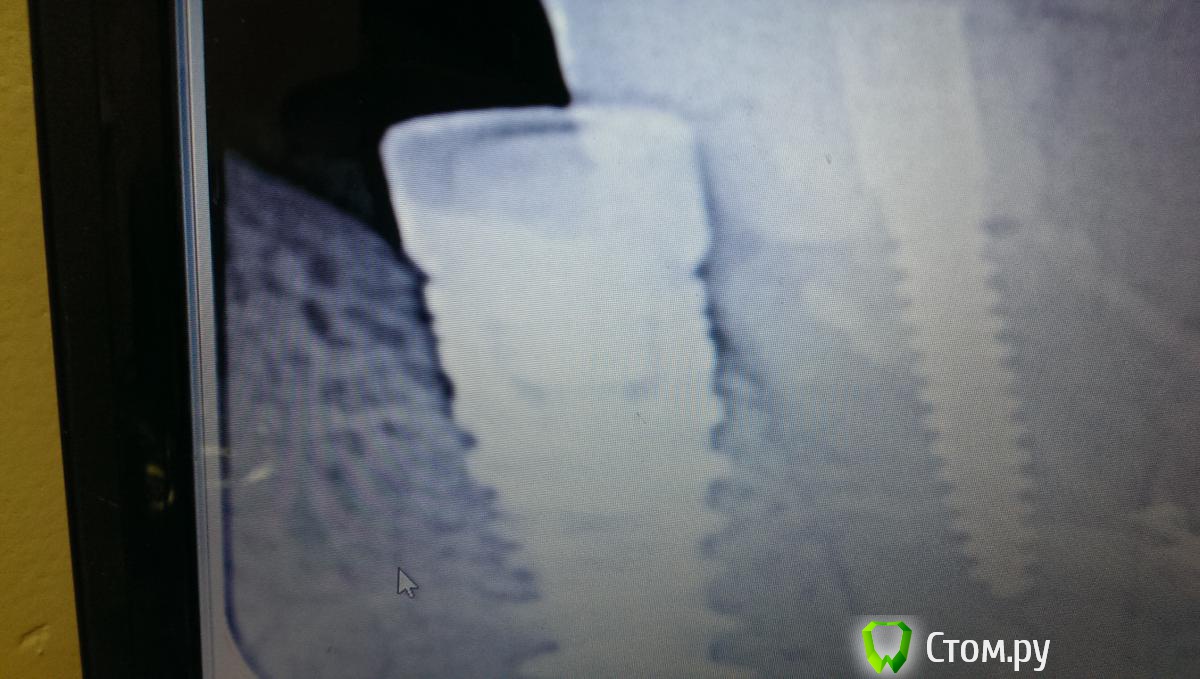

kriokov Опубликовано 13 мая, 2014 Поделиться Опубликовано 13 мая, 2014 (изменено) Сегодня бился бился, намертво сидит формирователь. Завтра будем решать,что делать, сделал снимок и отпустил. image.jpgснимок какой то интересный, такое впечатление, что формик в зуб упирается (во рту как?) Изменено 13 мая, 2014 пользователем kriokov Ссылка на комментарий

art700 Опубликовано 13 мая, 2014 Поделиться Опубликовано 13 мая, 2014 Непонятно там почему. Наложение видимо, но имплант близко довольно стоит, щипцами из-за этого неудобно откручивать. Ссылка на комментарий